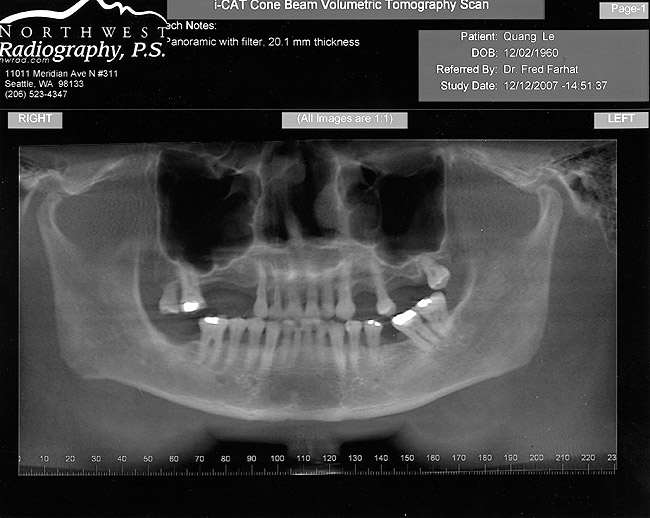

Figure 1  Buccal and radiographic views of posterior edentulism with significant sinus pneumatization in the molar region.

Figure 1

Figure 2  Buccal and radiographic views of posterior edentulism with significant sinus pneumatization in the molar region.

Figure 2

Figure 3  Buccal and radiographic views of posterior edentulism with significant sinus pneumatization in the molar region.

Figure 3